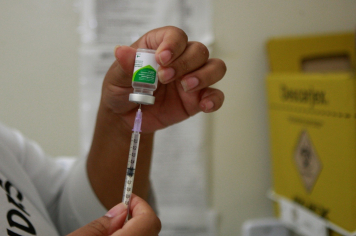

- Saúde